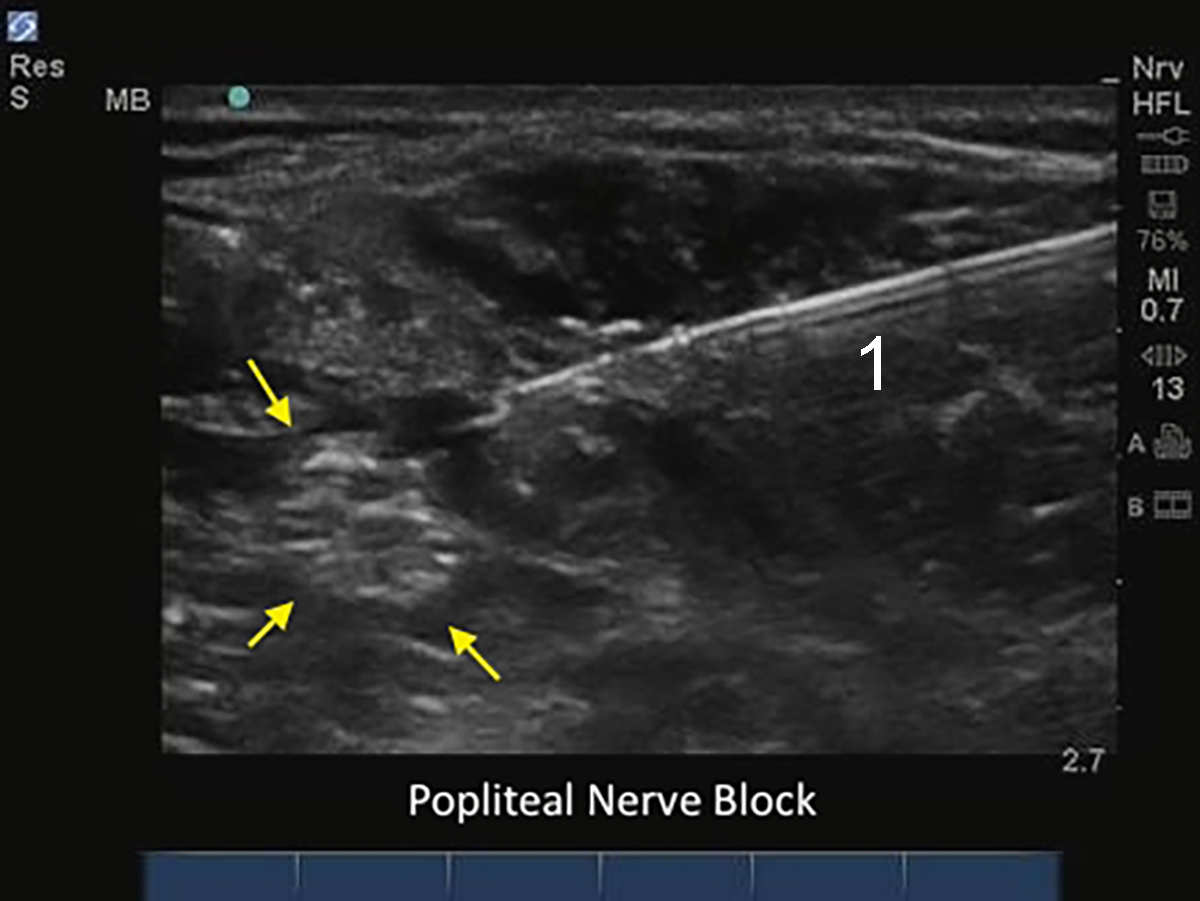

M-Turbo: Popliteale Nervenblockade mit Nadel

1. Nadel